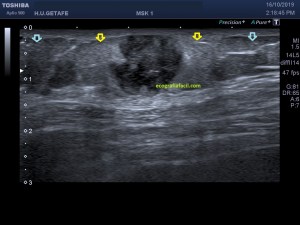

En la imagen 3 ves una imagen de un lipoma, mide 7 cms, la huella de la sonda mide 5cms, la «panoramic view» posee una regla centimetrada que sigue el contorno de la imagen, justo en la profundidad de la misma y lo marca la flecha amarilla. La profundidad la marca la flecha roja y la flecha blanca marca el rango centimetral de los 5cms, fíjate que la línea blanca es ligeramente mayor cada 5 cms. Sirve de referencia, como en la imagen 4 donde ves una colección en el glúteo de más de 10 cms.

Técnicamente es lo mismo, ambos dispositivos hacen una suma de imágenes que se plasman en un resultado final estupendo. Toda la escena más pequeña, pero más alargada que te da percepción de toda la magnitud de aquello que pretendes estudiar, te quita algo de detalle, pero te sirve para medir perfectamente y además puedes incrementar y mover la imagen con tu track ball…

Podemos medir valores superiores a los 15cms con alta calidad de imagen…podemos llegar a medir valores por encima de los 25 cms…es verdad que no todos los equipos tienen este ajuste ecográfico, es decir, es una aplicación y por tanto hay que pagarla.